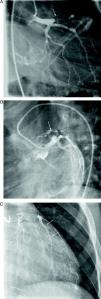

At the age of 11, he was referred to the pediatric cardiology department due to angina and exertional dyspnea of one month's evolution. The chest X-ray revealed a round area of calcification in the upper left portion of the cardiac silhouette (Fig. 1). There were no alterations on the electrocardiogram (ECG). Echocardiography showed ectasia of the left coronary artery of 4 and 5mm in the proximal and distal segments, respectively, with no wall motion abnormalities or mitral regurgitation. During nuclear perfusion scan with exercise, the patient reported chest discomfort at peak exercise, when the ECG showed ST-segment depression in II, III, aVF, V5 and V6. The nuclear perfusion scan during exercise showed severe hypoperfusion in the apex and the anteroseptal, apical-septal, and anteroapical segments and moderate hypoperfusion in the mid and basal segments of the anterior, inferior and inferoseptal walls, corresponding to the territories of the left anterior descending (LAD) artery and the right coronary artery (RCA), the alterations being reversed at rest. Cardiac catheterization revealed occlusion of the proximal segment of the LAD downstream of the calcified aneurysm, with retrograde filling by collateral circulation from the proximal branches of the left coronary artery (Fig. 2), and of the proximal RCA, with retrograde filling by collateral circulation from the left coronary artery (Fig. 3). Left ventriculography demonstrated good function, with no ventricular aneurysmal alterations.

(A) Left coronary angiography: left anterior descending artery occluded distal to the calcified aneurysm (arrow). (B) Left coronary angiography showing calcified aneurysm (arrows). (C) Left coronary angiography: occluded left anterior descending artery with late retrograde filling by collaterals from the left coronary circulation (arrows).